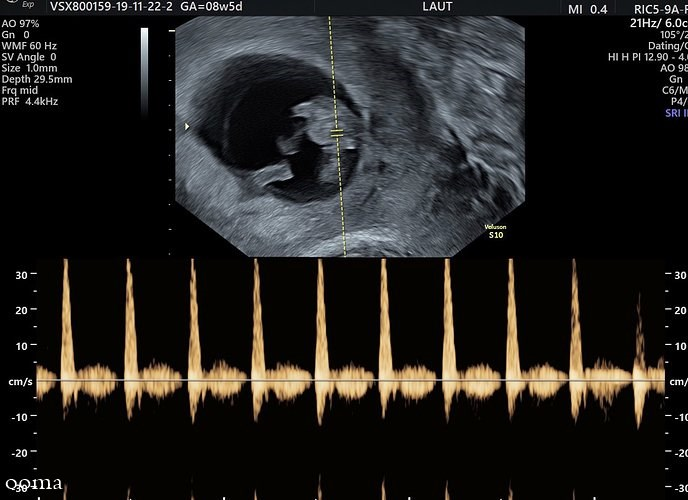

سونوگرافی نیز یکی از آزمایش معمول بارداری است که چندین بار در طول بارداری برای کمک به پزشک در تشخیص شرایط مختلف انجام می شود. برای انجام این آزمایش روی یک تخت می خوابید و پزشک رحم شما را اسکن می کند. این آزمایش از امواج صوتی برای ایجاد تصویری از کودک شما استفاده خواهد کرد و اغلب برای بررسی رشد و سلامت کودک شما به کار می رود.

از آنجا که سونوگرافی تصویری از کودک شما ایجاد می کند، می تواند جنسیت کودک شما را نیز از روی ویژگی های ظاهری نشان دهد. اکثر پزشکان سونوگرافی تشخیص جنین را در حدود هفته های 18 تا 21 تنظیم می کنند. توجه داشته باشید که نتایج تشخیص جنسیت با روش سونوگرافی همیشه به طور صد در صد دقیق نیست؛ زیرا ممکن است جنین در هنگام سونوگرافی در وضعیت نامناسبی قرار داشته باشد و اندام تناسلی او که مهمترین عامل تشخیص جنسیت با این روش است کاملا مشخص نباشد.